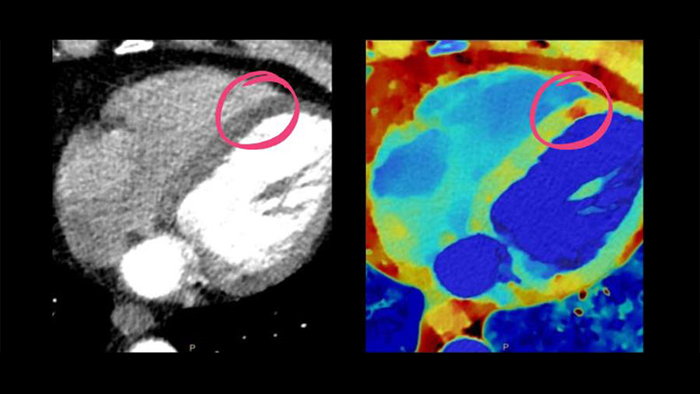

• Cardiac CT: Proven CT cardiac imaging capabilities, dose management tools, and exclusive clinical insights from detector-based Spectral CT.

Spotlight on: Cardiac CT (Spectral CT 7500)

See beyond routine cardiac imaging with the additional clinical information of Spectral CT for advanced cardiac applications. Learn how the Spectral CT 7500's "Always On" Spectral CT workflow helps you meet the needs of all your patients with zero compromises.

Spectral CT 7500

Unlock the full potential of CT as a non-invasive cardiac diagnostic tool.